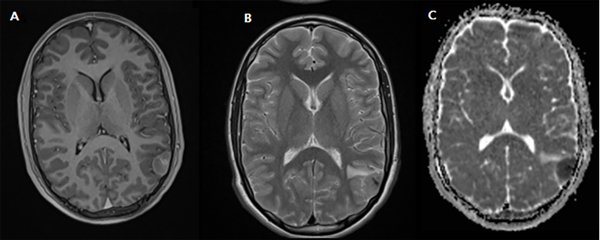

Paciente de 14 años, previamente sano, consulta en guardia externa de hospital de cercanía por episodio de afasia de expresión seguido por convulsión tónico clónica generalizada con periodo postictal que requiere intubación orotraqueal y derivación a UTIP de Hospital de Niños Ricardo Gutiérrez para complementar estudios. Se realiza tomografía computada (TC) de cerebro simple y en el informe preliminar no se evidencian alteraciones significativas. Se procede a la extubación electiva y posterior pase a sala de Clínica Médica. Se realiza resonancia magnética (IRM) de cerebro con y sin contraste donde se observa lesión extraaxial de bordes definidos a nivel parietal izquierdo que contacta con el giro angular, de 29 mm. de diámetro anteroposterior, 15 mm de diámetro transverso y 20 mm de desarrollo cefalocaudal. La lesión restringe en la técnica de difusión. En el T2 se evidencian imágenes con vacío de flujo evidenciando estructuras vasculares. El examen no demuestra lesión ósea. El refuerzo postcontraste es franco aunque heterogéneo y no presenta realce dural adyacente a la lesión. (Fig. 1). En la TC simple de cerebro, en ventana ósea, no se evidencia reacción periostica perilesional.

Figura 1: IRM de cerebro con y sin contraste, A) T1 C + Axial. Lesión extra axial a nivel del giro angular, se observa refuerzo tras la administración de gadolinio B) T2 Axial. Se evidencia edema perilesional vasogénico C) DWI ADC Axial. Tumor que restringe a la técnica de difusión.